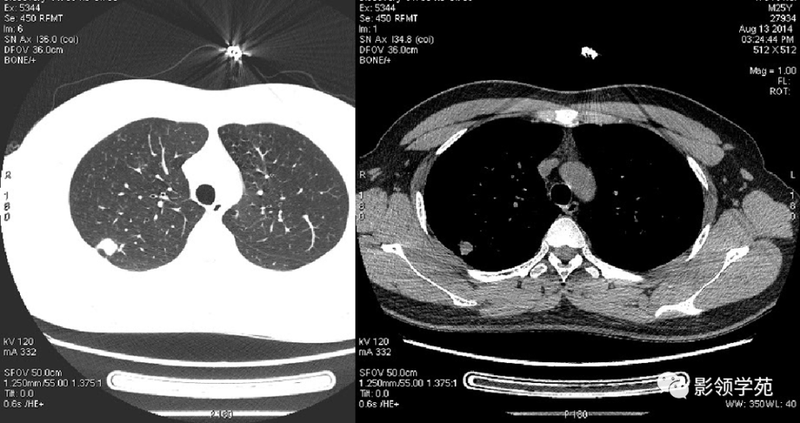

(1)较大含空洞性肿块,洞壁较厚,大于15mm,空洞外壁有分叶、毛刺,洞壁凹凸不平有壁结节,增强可见不规则强化,周围未见明显卫星病灶时,首先考虑周围型肺癌;癌性空洞洞壁一般肺门侧较厚,空洞多偏于外侧,伴有同侧淋巴结肿大更支持肺癌诊断。